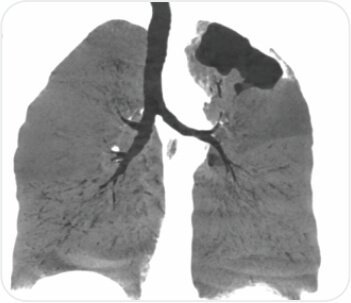

CT thoracic angiograph

CT chest with thoracic angiogram revealed bilateral cavitary lesion with hypertrophied collateral arteries predominantly supplying the right upper lobe cavity. FOB done showed active bleeding from right upper lobe bronchus.

Watanabe sphigot occlusion of anterior subsegment of right upper lobe + glue instillation of right apical and posterior sub segment followed by bronchial artery embolization was done.